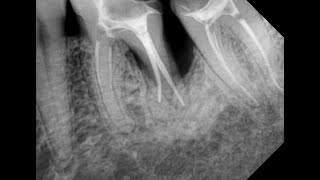

Пульпит хронический фиброзный – это одна из форм пульпита, заболевания полости зуба, которое характеризуется воспалением пульпы зуба и постепенным замещением ее соединительной тканью.

При хроническом фиброзном пульпите воспаление развивается медленно, и процесс замещения пульпы соединительной тканью протекает постепенно. В результате зуб теряет свою нормальную функцию и чувствительность. Часто такие зубы требуют лечения или удаления.